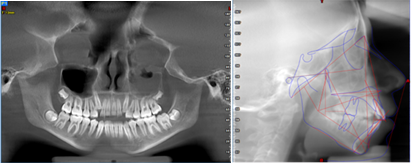

A través de los cortes tomográficos (Figura 3) se pudo observar que la rama mandibular derecha medía 43.85 mm y la izquierda 39.53 mm dando una diferencia de 4.34 mm lo que evidencia que la asimetría que presenta la paciente es a causa de la discrepancia de tamaño de las ramas mandibulares (A).

En el corte a nivel de la articulación temporomandibular izquierda se observó un aplanamiento del cóndilo con áreas de cambios osteoartríticos leves (B); en la articulación temporomandibular derecha el cóndilo se encuentra con una severa osteoartritis que muestra una imagen hipodensa a nivel condilar compatible con un quiste subcondral (C).

Plan de tratamiento: Debido a todo lo expuesto se decidió colocar un aparato de avance mandibular tipo monoblock para recapturar el disco. Para ello se inició con la realización de una mordida constructiva para la confección del aparato, se llevó a una coincidencia de las líneas media y un adelantamiento mandibular de 3 mm (Figuras D, E y F). Posteriormente se envió los registros para la confección del dispositivo de avance mandibular tipo monoblock (Klammt Clase II) que fue instalado en marzo del 2023 constatando de que se encuentre totalmente adaptado (G), las indicaciones de uso fueron más de 20 horas al día aconsejando que la paciente se lo retire únicamente para comer y para el aseo respectivo. Los controles se realizaron a las 2 semanas y después con una frecuencia mensual durante 12 meses.